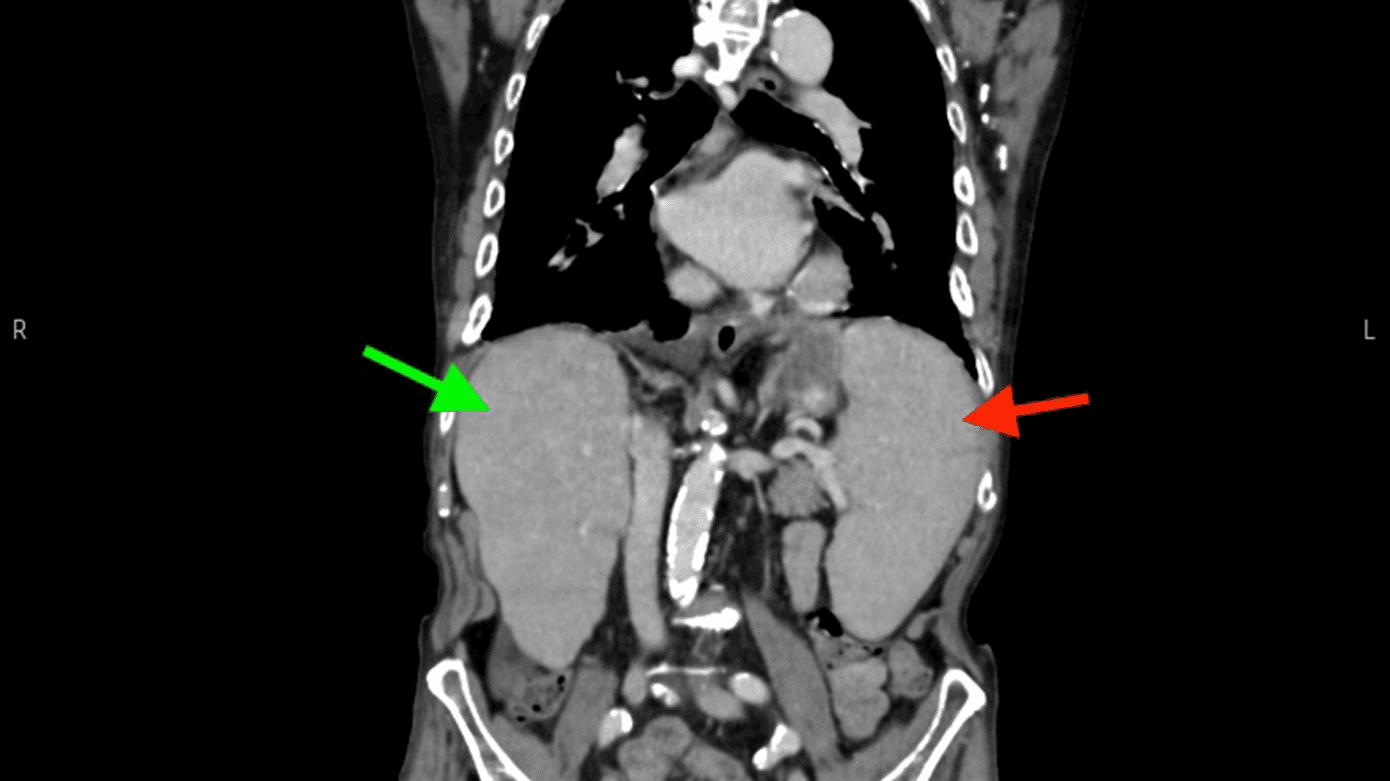

En 86-årig etnisk dansk mand diagnosticeret med letkæde lambda myelomatose i 2. linjebehandling med kemoterapi blev fulgt i hæmatologisk regi siden 2019. I løbet af et år havde patienten ca. ti indlæggelser med nedsat almen tilstand, recidiverende feber og forhøjede infektionsparametre uden fokus. Patienten opnåede kun kortvarig lindring på intravenøs antibiotisk behandling førend næste indlæggelse. En CT under en af indlæggelserne viste både hepato- og splenomegali (Figur 1). Blodprøver viste pancytopeni med hæmoglobin < 7,0 mmol/l, leukocytter < 2,0 mia./l og trombocytter < 60 mia./l, som initialt blev tilskrevet enten nytilkommet myelodysplastisk syndrom (MDS) eller progressiv myelomatose.

Grundet langvarig uafklaret feber blev der udbedt tilsyn fra infektionsmedicinsk afdeling. Ekspositioner viste en ekstensiv rejsehistorik i både Asien, Sydamerika og Sydspanien. Der anbefaledes supplerende mikrobiom 16S/18S på ethylendiamintetraacetat (EDTA)-blod. Denne var positiv for Leishmania. Sekvensering af internal transcribed spacer (ITS)-genet identificerede L. donovani/infantum-komplekset, hvilket bekræftede diagnosen visceral leishmaniasis. Dette forklarede patientens hepato- og splenomegali samt pancytopeni. Den seneste knoglemarvsbiopsi blev reevalueret af patologerne, men uden fund af amastigoter, som kan ses ved leishmaniasis. Patienten opstartede intravenøs liposomal amphotericin B og mærkede klar bedring allerede efter første behandling. Kort efter anden dosis ophørte feberen, og patientens biokemi bedredes. Hæmatologisk set var myelomatosen under kontrol, og patienten blev sat i behandlingsfri observation efter udtrapning af steroid.